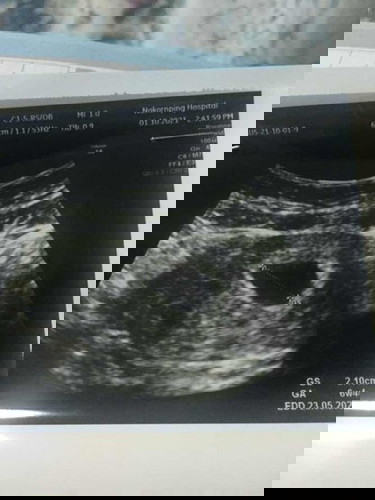

อัลตร้าซาวด์ตอน6วีค1วัน

คุณแม่บ้านนี้ตรวจเจอตอนเบบี้น้อย 6w1dค่ะ ขอให้น้องแข็งแรงกันทุกๆบ้านเลยนะคะ ❤️👶